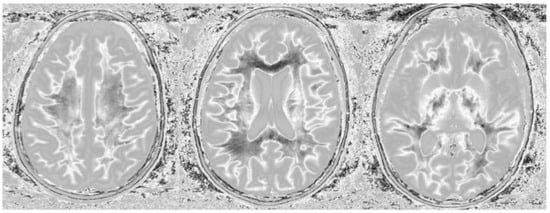

Figure 11.

Divided Subtracted Inversion Recovery (dSIR) in a patient with multiple sclerosis (MS). T2-FLAIR (left), inversion recovery (IR) T1-weighted (middle), and wide-domain dSIR with TIshort = 450 ms and TIlong = 850 ms (right) images through the pons in a patient with MS. A large plaque is obviously present in the left hemipons on the dSIR image (red arrow in the image on the far right). The contrast in this image is due to changes in white matter T1. The change in T1 is insufficient to cause noticeable contrast on the IR T1 image (middle). The change in T2 is insufficient to cause noticeable contrast on the T2-FLAIR image (left).